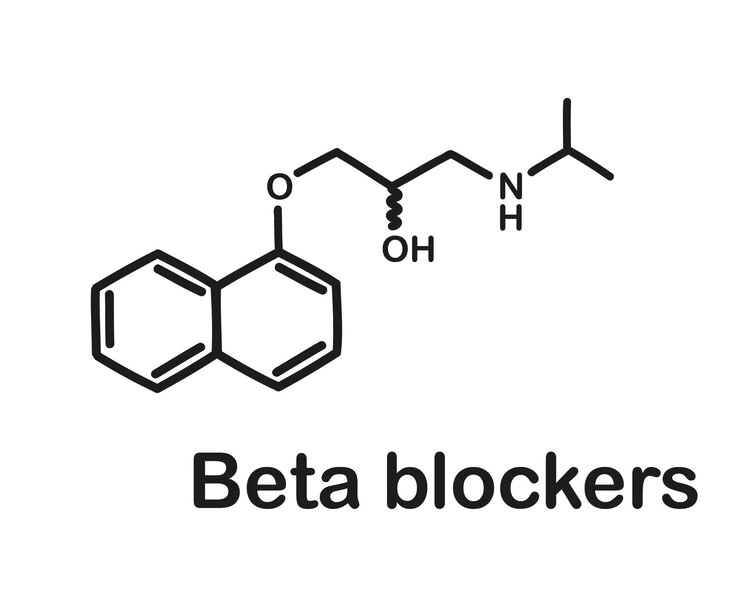

Seizures in the Setting of Metoprolol Overdose

Beta-blockers are commonly prescribed for several conditions, including hypertension, cardiac arrhythmias, coronary artery disease, and heart failure. Their physiologic effects...Read More